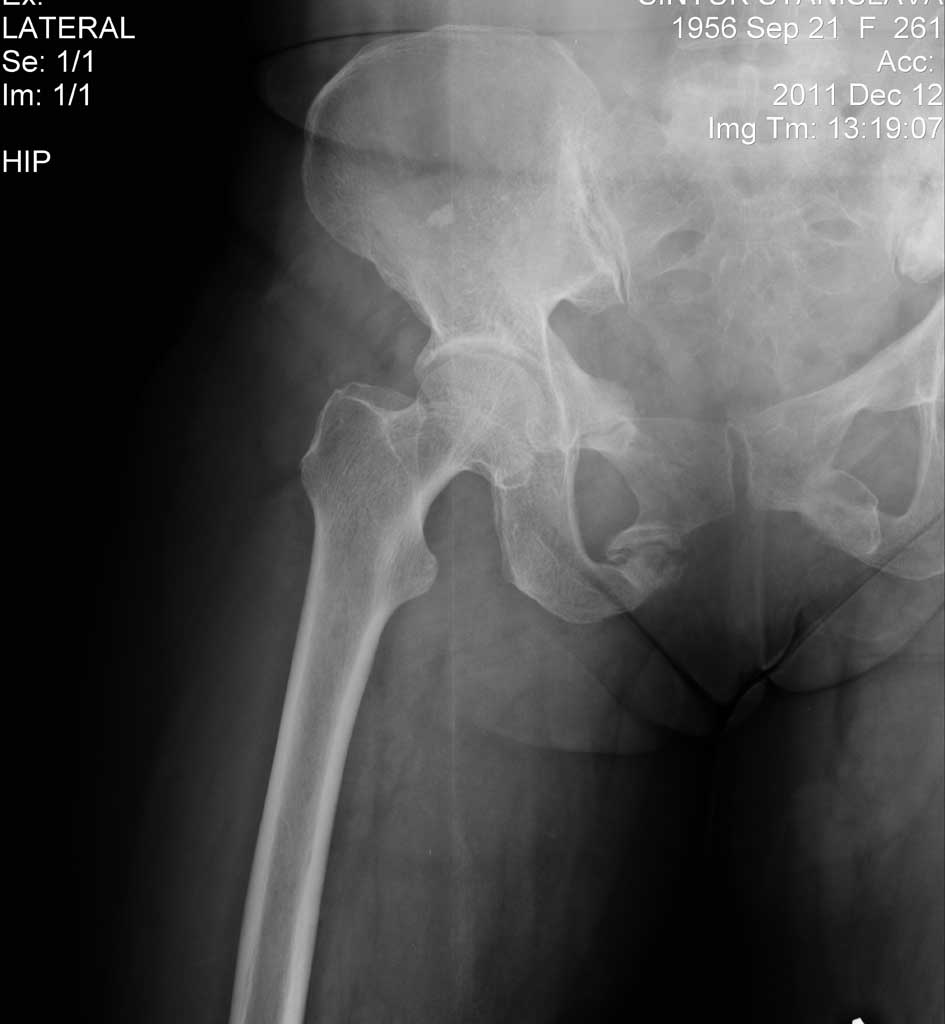

Травма 3 года назад , перелом типа "бабочки".В настоящее время беспокоят боли в области лонной кости при стоянии и ходьбе, в покое все спокойно.

Данных для нормального разбора не хватает, материал предоставлен не в полном объеме. Если про возраст пациента можно догадаться по записи на рентгене, то остальные важные детали анамнеза, например, профессия, активность, сопутствующие заболевания, проведенное лечение, а также результат клинического осмотра отсутствует.

А так изолированные переломы таза типа "бабочки" срастаются в течение 3-4 недель без последствий, и проявления клинических симптомов после 3 лет говорит о последствии перелома - нестабильности таза. Для нормального снимка таза тубус рентгена можно было сдвинуть на 15 см влево и, кстати, там с левой стороны видно, что перелом с вовлечением левой стороны таза. Нужно полное обследование таза, рентген: прямой, инлет и оутлет, а также КТ срезы.

переломы срослись в порочном положении. такие смещение обычно сочетаются с повреждением в заднем полукольце. его надо искать

Доброго времени суток! судя по рентгенограмме у пациента ложный сустав лонной кости. Как сложатся остальные мнения не знаю но мы закрыто зафиксировали бы винтом тем самым разрушается замыкательная пластина и склероз в зоне ложного сустава, малотравматично и низкий риск осложнения я имею ввиду нагноение раны, а еще до операции провести КТ, посмотреть задний комплекс, нередко выявляется переломы боковой массы крестца со сдавливанием крестцового отверстия боли могут быть связаны с неврологией тогда тактика может измениться в отношении фиксации заднего комплекса. С уважением Ерсин Жунусов.